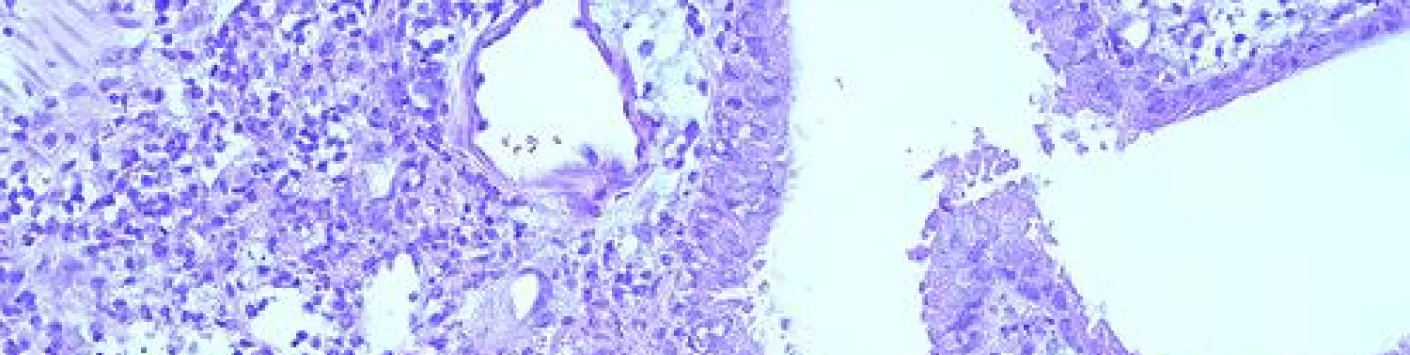

➡️ Une étude réalisée par des chercheurs du département des maladies infectieuses (FARAH/Faculté de médecine vétérinaire Université de Liège) vient de mettre en évidence le rôle important des monocytes Ly6Chi dans la régulation des réponses immunitaires au niveau de certaines maladies infectieuses.

➡️ "Au cours de l’étude que nous venons de publier dans Science Immunology, explique Bénédicte Machiels, Chercheuse qualifiée F.R.S.-FNRS FNRS à l' Université de LiègeUniversité de LiègeUniversité de Liège, nous nous sommes intéressés aux mécanismes régulateurs induits par des virus persistants, les gammaherpèsvirus (γHVs) - des virus extrêmement prévalents tant chez l’homme que chez l’animal- ayant co-évolués avec leur hôte depuis des millions d’années."